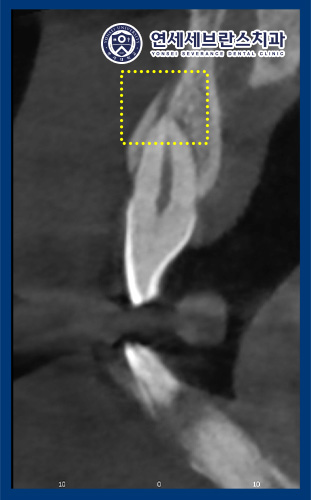

또한 CT를 촬영하여 확인해 보니,

왼쪽 위 치아는 치조골 골절을

관찰할 수 있었습니다.

발치 후 식립 전 CT를 통해

식립할 위치를 확인하고

그에 맞춰 식립을 진행하였습니다.